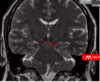

State where this stroke has occured

Right MCA